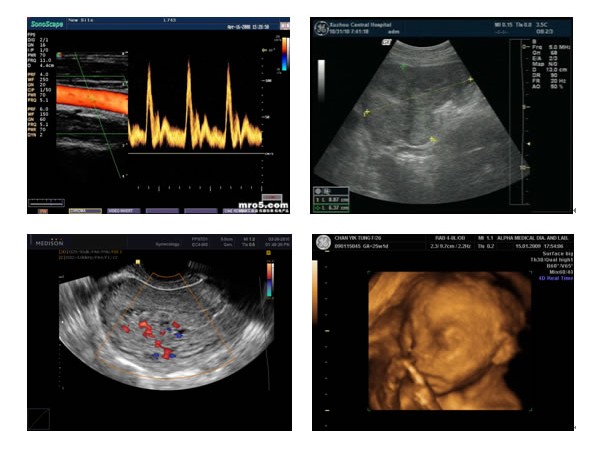

產(chǎn)品名:菲力姆噴墨B超膠片 醫(yī)用膠片 醫(yī)用干式膠片

企業(yè)名:合肥菲力姆科技有限公司

最新菲力姆噴墨B超膠片 醫(yī)用膠片 醫(yī)用干式膠片招商